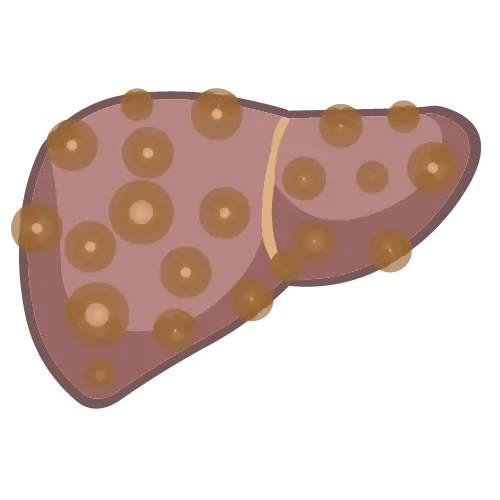

Fino a pochi anni fa, l’unico modo per valutare la presenza e il grado della fibrosi epatica era la biopsia del fegato, un esame invasivo che consiste nel prelievo di un frammento di tessuto epatico con un ago.

La biopsia, pur essendo considerata a lungo il “gold standard” diagnostico, comporta rischi e disagi non trascurabili: richiede anestesia locale, può causare dolore e, seppur raramente, gravi complicanze come emorragie, oltre ad avere costi elevati e necessitare di tempo per l’analisi istologica.